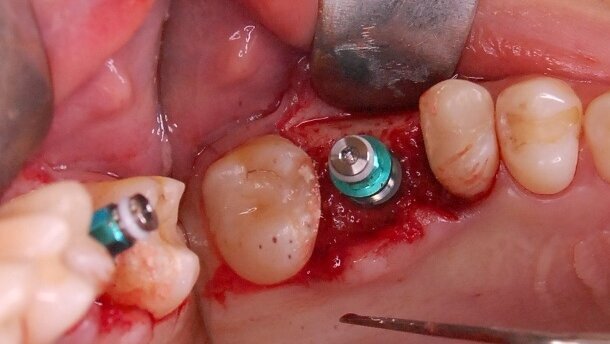

W kolejnym etapie implant TS3 5,0 x 10 (Osstem Implant) wprowadzono przy prędkości 35 obr./min i osadzono równo z poziomem kości ze stabilizacją pierwotną 35 Ncm. Założono śrubę zamykającą, a ranę zaszyto. Wykonano rtg kontrolne. Pacjentka po zabiegu przyjmowała antybiotyk Dalacin C 0,3 po 1 kapsułce co 8 godz., przeciwbólowo Aulin po 1 tabletce co 12 godz. w razie bólu.

Po 7 dniach wykonano wizytę kontrolną, podczas której pacjentka nie zgłaszała dolegliwości. Stwierdzono wygojenie rany i zdjęto szwy (Ryc. 9). Po 6 miesiącach od wykonania zabiegu, poprzez nacięcie błony śluzowej w znieczuleniu miejscowym, odsłonięto implant, założono śrubę gojącą 6,5 x 3. Wykonano kontrolne badanie CBCT w celu oceny ilości uzyskanej kości wokół implantu (Ryc. 10). Po następnym zdjęto szwy, a po kolejnym wykonano wycisk do korony na implancie. Po odkręceniu śruby gojącej, przed wykonaniem wycisku, stwierdzono wygojone, zdrowe dziąsło wokół wszczepu. Wycisk silikonowy z transferem, kęsek zwarciowy i wycisk alginatowy zębów żuchwy przesłano do laboratorium protetycznego w celu dobrania łącznika i wykonania korony porcelanowej napalanej na metal (Ryc. 12).